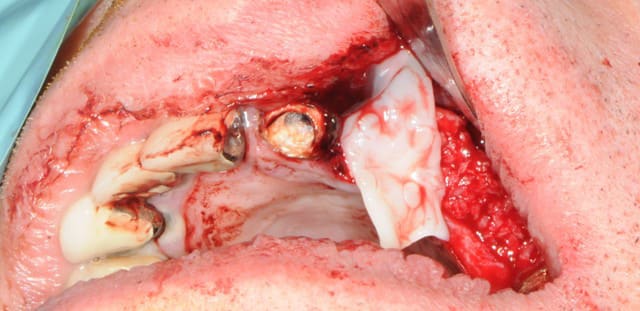

Tient, pour toi, petit montage photos, du cas de ce matin.

1er cas d'expansion fait suite formation Sallanches.

C'est pas un gros cas complexe, mais juste assez difficile, et juste assez cool pour moi.

Patiente adressée suite à une ré-hab prothétique fait en 2010, perte de la canine 6 mois après...donc stellite plutôt mobile, comme la 14 et bientôt la 37, mais bon, on commence le projet implanto.

Exo de la 23 + implantation immédiate

Expansion kit Meissegner et lame 15

Pose de 2 implants (13 et 11)

Pose 22 impossible, j'ai tenté, mais crak, bof, j'ai placé en 24 et 25.

Un peu de granules osseuse (23)

Les photos sont de ma nouvelle 2e assistant implanto.

Dans l'ordre pour le cas montré pour implants 11 et 13

1-Disque sur la crête

2-Lame 15 impactée (sommet crête et en vestibule (décharges)

3-Ciseaux à os (bone chivel)

4-Forêt 1.2 mm

5-Expanseur rotatif (A-B-C-D-E)

6-Pose implant